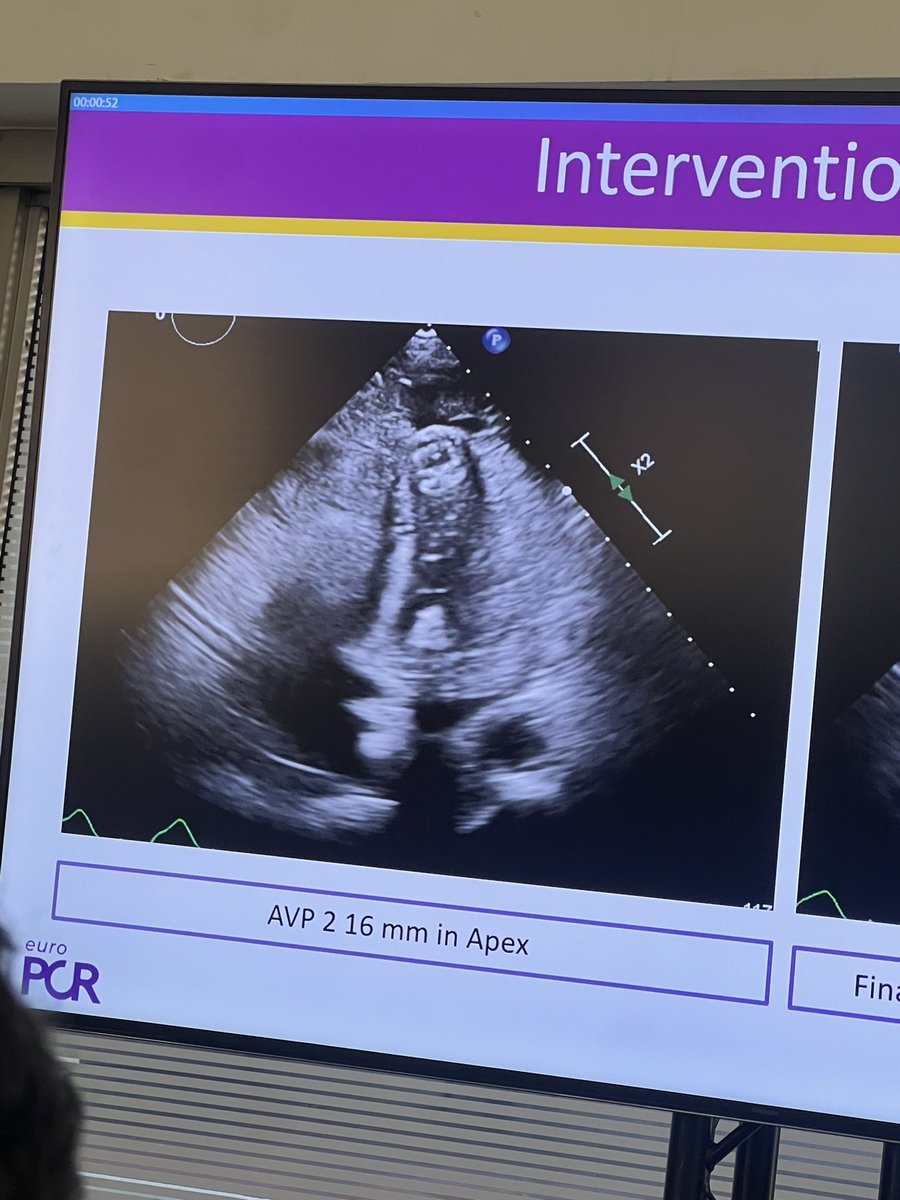

Amazing case by Fadi Sawaya of #TAVRinTAVR procedure with #Unicorn +additional stenting! #Laceration doesn't prevent completely the #coronary #obstruction but it allowed to treat it easily! #EuroPCR 25 PCRonline 🫀 Don't miss this EuroIntervention with a dedicated Expert consensus!